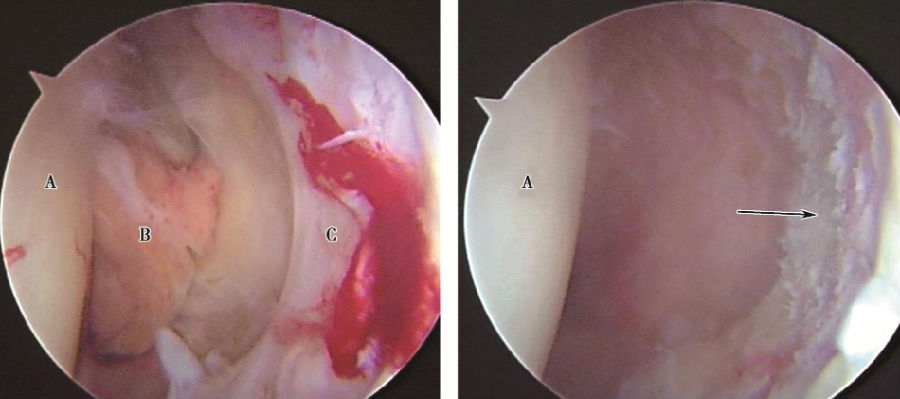

关节镜从经耻骨联合水平线与经髂前上棘垂线的交点处进入,保持其与冠状面和矢状面各成45°角,由外下向内上从关节囊前侧进入关节腔,使用球形磨钻磨去增生组织及硬化骨,再用刨削器彻底清理髋臼窝增生组织,修整盂唇,成形髋臼,目视下观察股骨头与重定位的新髋臼,确保头-臼同心圆匹配,最后使用射频行关节腔内止血后拆除关节镜(图3)。

图3 关节镜下可见圆韧带肥厚,盂唇增生A:股骨头;B:圆韧带;C:盂唇;箭头示镜下清理髋臼卵圆窝内增生组织,代偿性肥厚的盂唇已被修整。

关节镜手术本身创伤小,既能去除患髋关节内增生的组织及硬化骨,同时对关节内尚正常的结构和关节面的破坏小;而且关节镜手术显露清晰,可以直视下尽可能恢复重定位后的髋臼与股骨头的同心圆关系,使两者良好包容。